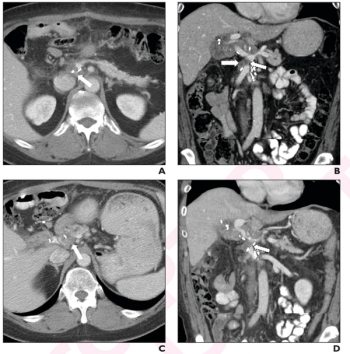

For patients who had post-op recurrence after a Whipple procedure for pancreatic ductal adenocarcinoma (PDAC), between 80 to 86 percent of follow-up CT exams revealed new or increased soft tissue.